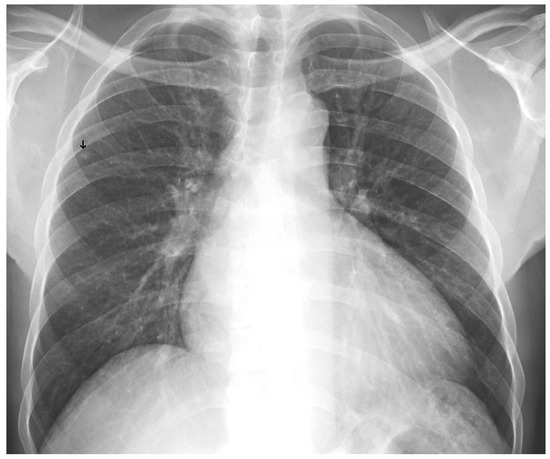

Before training, radiologists reviewed and verified the images, applying annotations using a proprietary software application (Figure 1). The dataset exhibited a significant class imbalance, reflecting the real-world prevalence of the pathology. For training binary classifiers, studies with definitive labels (1.0 for present, 0.0 for absent) were used. In contrast, studies with missing labels for a specific finding were excluded from the loss calculation for that task. Table 2 shows the distribution for a selection of key labels. The list of pathologies was selected based on the availability of labeled data, balanced with clinical importance for the ED. The ‘normal’ and ‘abnormal’ pools included cases with pathologies beyond the specifically targeted list; these were categorized under the general “yesfinding” class.

Figure 1. All labeled images were proofed by a radiologist who manually drew a region of interest around the pathology and assigned a finding, as shown here for an alveolar opacity circled by the dashed line.